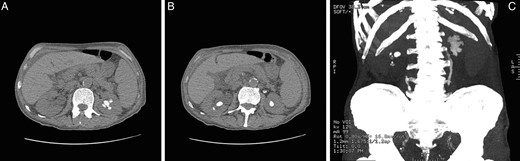

The aetiology of his RF was attributed to extensive bilateral ureteric calculi and a left-sided partial staghorn calculus, presumably of uric acid composition (Fig. 1).

Computed tomography of kidneys, ureters, bladder images demonstrating stone load in a 79-year-old male with CMML, prior to treatment with rasburicase. (A) Partial left-sided stag horn calculi. (B) Bilateral lower pole calculi. (C) Coronal reconstruction demonstrating total renal and ureteric stone load.